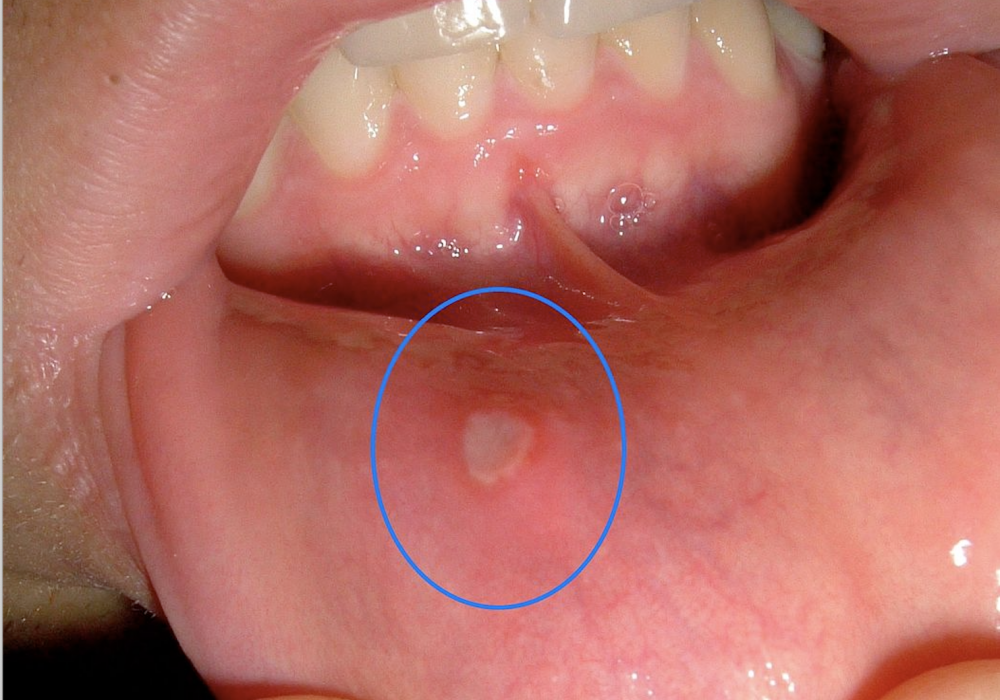

口腔溃疡(Canker sores, also called aphthous ulcers)是一种非常常见的疾病,最大的特点是反复发作。很多人在一生中都会有一次或者数次的口腔溃疡,有些人甚至每个月会有口腔溃疡。如果你是个吃货,这个烦恼体会会更加深刻。一般来说,口腔溃疡会持续一周到两周的时间,每个口腔溃疡的大小大概是3毫米到5毫米,成圆形或者卵圆形。

口腔溃疡可以分为单纯性的和复杂性的。单纯性的口腔溃疡是每年多次发作的一个或者数个口腔黏膜的溃疡,一般不会持续超过14天。这种口腔溃疡也是最常见的口腔溃疡。复杂性的口腔溃疡不仅累积口腔,还累及阴部。它的大小可以在一个厘米以上,持续时间可长达4到6周左右。如果是复杂性的口腔溃疡,还需要排除白塞氏病---一种免疫系统受累的综合征。

口腔溃疡在头一两天一般会是针尖样的小溃疡,到第三、四天的时候会达到最大,稳定之后,在一周到两周之间开始愈合。幸运的话可能四到五天就愈合了,但是大多数人需要10到14天的时间。